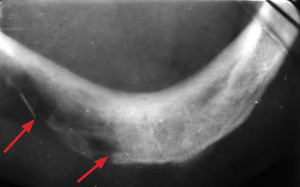

Metodą z wyboru jest leczenie chirurgiczne, w razie wskazań skojarzone z uzupełniającym napromienianiem. U chorych będących na granicy operacyjności zabieg może być poprzedzony chemioterapią neoadjuwantową. Alternatywą dla leczenia chirurgicznego jest radioterapia. U osób leczonych z powodu raka wargi dolnej za pomocą brachyterapii lub teleradioterapii nie ma możliwości oceny mikroskopowej radykalności leczenia. W 7-10 proc. przypadków powstają po leczeniu ubytki czerwieni wargowej oraz martwica popromienna żuchwy (osteoradionecrosis mandibulae), chociaż dzięki zastosowaniu nowej techniki naświetlań IMRT (tzw. dose painting) odsetek ten się sukcesywnie obniża. Na ryc. 3 przedstawiono zdjęcie zgryzowe żuchwy, na którym strzałkami zaznaczono obszar popromiennej martwicy kości. Stała utrata śliny, związana z niedomykalnością szpary ustnej, może być przyczyną dysjonii, stanowiącej zagrożenie ciężkimi zaburzeniami rytmu serca. U chorych w młodym wieku wzrasta 275-krotnie ryzyko powstania po 20-25 latach wtórnych nowotworów popromiennych.